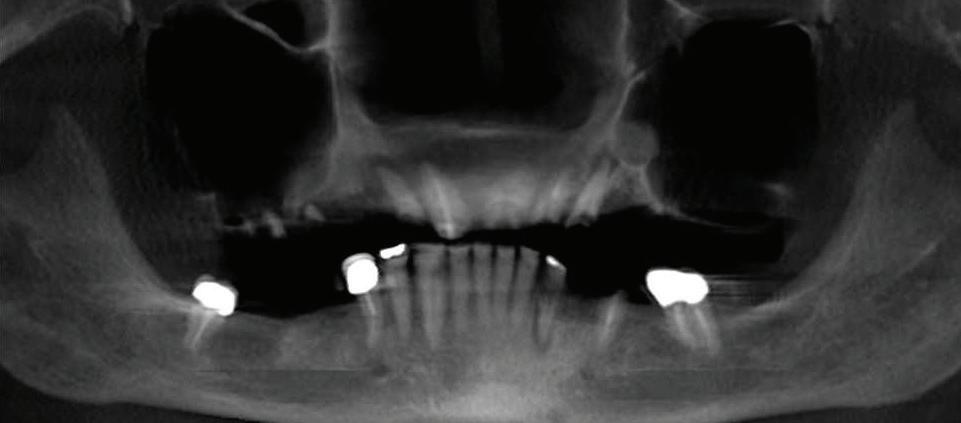

Can just four implants replace all of the teeth on the top or the bottom of your mouth? Thanks to advances in dental implant technology, that answer is a resounding yes.

Tooth loss is extremely common among adults, especially as we age. Rather than living with the discomfort and hassles of dentures, many people are opting for what is called “all-onfour” dental implant restoration.

An implant is a small titanium screw

that fits inside your jawbone and replaces the root-part of a missing tooth. Minor surgery is required to insert the implants. Once the implant is in place, a crown is attached to give you a highly realisticlooking and functional prosthetic tooth.

You do not need a dental implant for each and every one of your missing teeth. All you need is four precisely placed implants on the top of your mouth, and four on the bottom, to restore your full smile. That’s the beauty of the all-on-four. And because the implant is made of titanium, it has the unique ability to fuse to living bone and function as part of it. So eventually, the dental implant becomes part of the jawbone and serves as a strong, longlasting foundation for your new teeth.

Besides ensuring that your implants are permanently fixed in place, this bone fusion has another important benefit: it prevents future bone loss in the jaw. This helps to maintain a more youthful facial structure – and better oral health. But perhaps the biggest

Please see “All-On-Four,” page 61